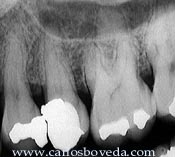

Segundo

Premolar Superior Izquierdo

El

paciente, de 39 años de edad, es referido a

nuestra consulta para tratamiento

endodóntico del segundo premolar superior

izquierdo.

Completamente

asintomático, este premolar

evidenció una clara área

radiolúcida apical en una

evaluación radiográfica

periódica. No responde a las

pruebas de vitalidad ni a las de

percusión. Luego de diagnosticar la

necrosis pulpar y comenzar con el

procedimiento endodóntico, puede

detallarse la filtración de saliva

en el borde inferior de la

restauración.